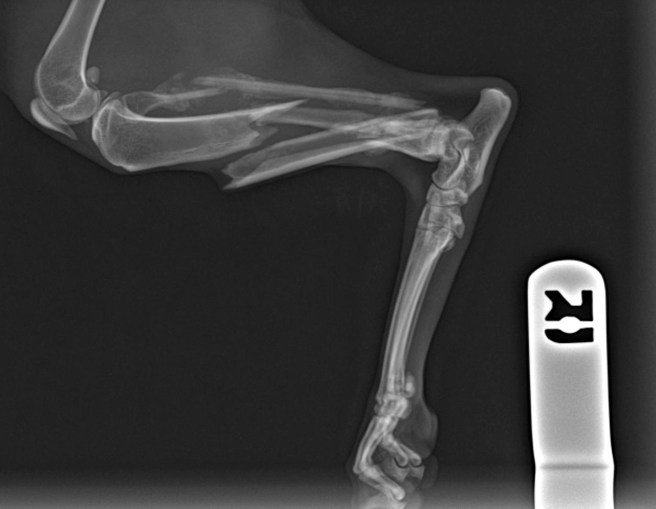

I believe a crime may have occurred with regard to Gloria, a NYC cat whose badly broken leg you see on an x-ray above. While there is no way to know how her leg was broken, we do know some facts, courtesy of John Sibley’s blog, and it is within those facts that I believe a criminal investigation is warranted.

Remarkably absent from the veterinary exam notes is any mention of the fact that this cat was suffering from a badly broken leg. I’m not a pet psychic but I can guess Gloria was in no small amount of pain, perhaps accounting for the “tension” noted in her behavioral exam.

Thankfully, Gloria was rescued by Pets Alive. They are not vets but after one day with Gloria, they realized something was wrong and brought her to their vet for an exam. Their vet determined her leg was broken beyond repair and amputation was required. She had the surgery the following day and is recovering well (donate to help with Gloria’s veterinary bills here). The veterinary surgeon determined that Gloria’s leg had been broken for at least a month prior to amputation.

NYCACC allowed Gloria to sit in a cage for weeks with a broken leg – long enough for her to catch a cold and be placed on the kill list. Neither veterinary exam noted her broken leg nor are there any notes about providing pain medications.